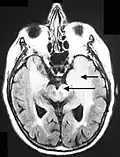

Secuencia FLAIR postcontraste de un caso de meningitis. Muestra la mejora de las meninges en el tentorio y en la región parietal, con evidencia de ventrículos dilatados.